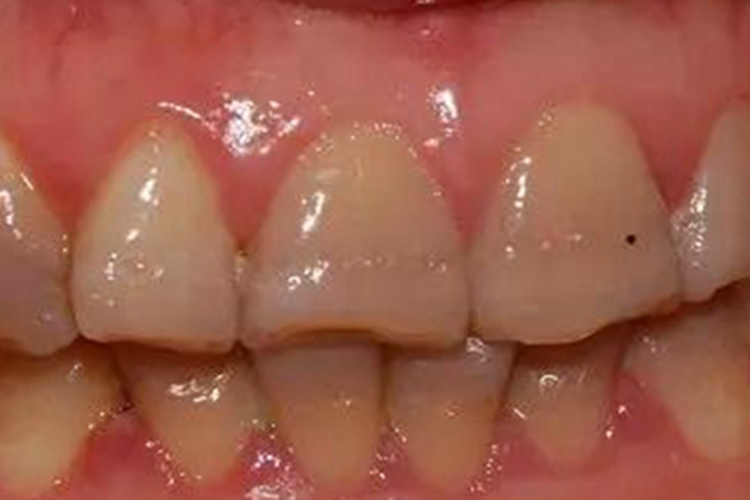

牙釉质发育不全严重时,患者牙齿表面可出现条纹状凹陷,呈并列的横沟,牙釉质表面呈棕褐色,牙齿易受磨损,顶端发生断裂,舌头舔舐时有摩擦感。